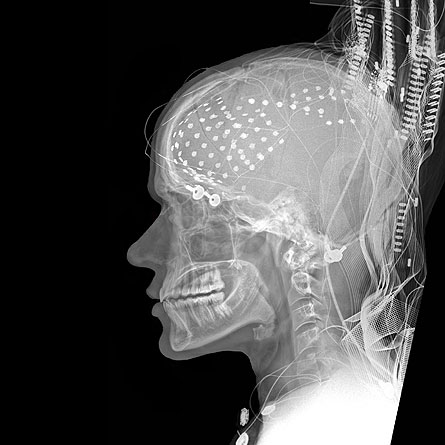

Now, patients with epilepsy are giving researchers split-second insight into language processing in Broca’s area. Three people with epilepsy had a rare surgery to implant electrodes in their brains. The surgery allows doctors to pinpoint the source of seizures and treat the condition while sparing parts of the brain that control language, vision and other important processes. The patients gave permission for Ned Sahin of the University of California, San Diego School of Medicine and his colleagues to measure activity in their brains during pre-surgery tests.

Those measurements showed that Broca’s area is able to do more than scientists had thought, including executing all steps from reading to speaking. The area recognizes words within 200 milliseconds of a person seeing them. Then it takes only another 120 milliseconds to mentally change the tense of a verb or make a noun singular or plural. By 450 milliseconds after first seeing a word, the brain is ready to silently articulate it.